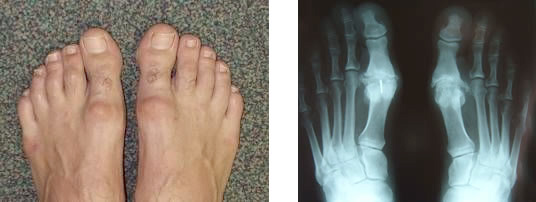

Il s’agit de l’usure de l’articulation métatarso-phalangienne du gros orteil. L’arthrose entraîne un enraidissement progressif de l’articulation d’où le terme « rigidus ». Cela se manifeste outre par la raideur, par des douleurs localisées sur l’articulation, et souvent par l’apparition de déformations appelées « ostéophytes » qui peuvent gêner le chaussage.

Il est clinique et radiographique.

Les radiographies mettent en évidence la destruction de l’articulation et son stade, permettant ainsi de choisir le traitement.